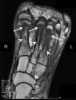

Charcot spine